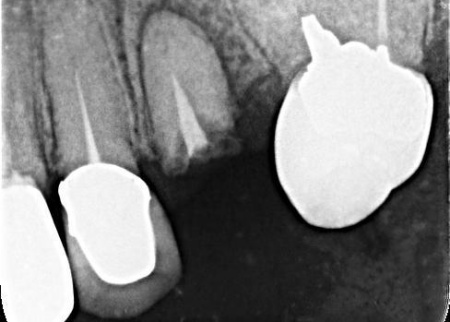

50代女性銀歯の下の虫歯を除去しセラミックで修復したケース

レントゲン像で金属の下に虫歯があり、患者さんは入れ替えを強く希望されました。

特に審美的な要求をされたため、セラミック修復の説明をし、治療の同意を得ました。